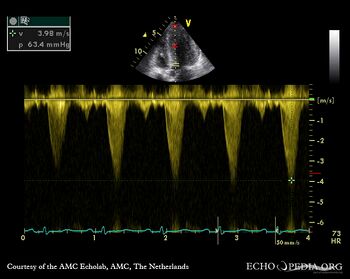

Continuous-wave doppler signal: dynamic gradient in LVOT